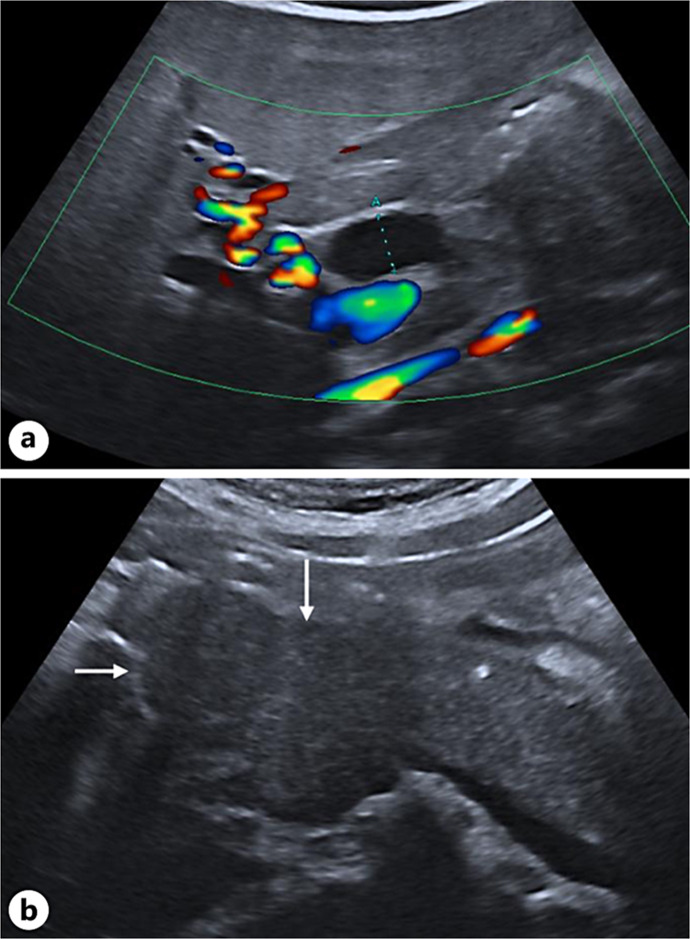

Case presentation: A 14-year-old adolescent presented to the emergency department with abdominal pain, vomiting, and jaundice. A combination of biological and radiological assessments led to the diagnosis of AIP. The patient experienced a swift and complete recovery without intensive treatment.